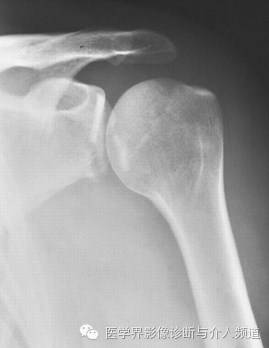

19、Hill-Sach’s骨折

肱骨头压缩性骨折。肱骨头向前脱位,由肱骨头撞击肩胛盂前缘造成,肱骨头后外侧压缩骨折。